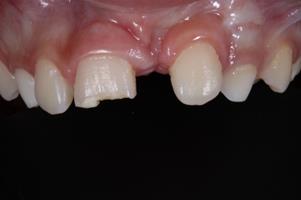

An 8-year-old male patient attended the Emergency Children's Dental Care at the Children's Specialties Clinic-Baby-Clinic of the State University of Londrina, for immediate treatment after a fracture in the right upper central incisor due to a fall during a school sports activity. On intraoral physical examination, a coronal fracture of the enamel and dentin was diagnosed without involvement of the pulp tissue (Figure 1). Response to the vertical and horizontal percussion test was not suggestive of endodontic and periodontal alterations, respectively, and impairment of the periodontal insertion was also ruled out through the mobility test in the buccal-palatal direction.On radiographic examination (Figure 2) confirmed the absence of periodontal and periapical involvement, as well as the absence of root fracture.